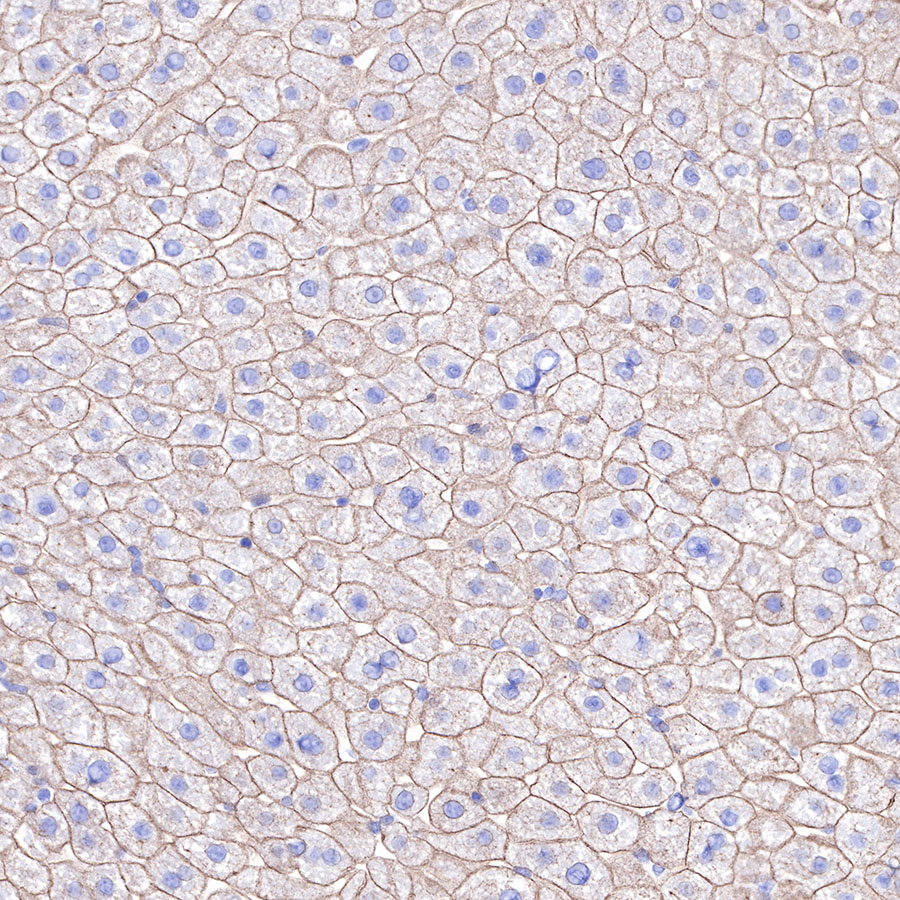

| IHC-P |

1:2000 |

Cytokeratins are proteins of cytoskeletal intermediate filaments, and their main function is to enable cells to withstand mechanical stress. In humans, 20 different cytokeratin isotypes have been identified. Cytokeratins 8, 18, 19, and 20 have been associated with bladder. Cytokeratin 18 (KRT18, also called K18), found in epithelial cells, is released from hepatocytes upon death.